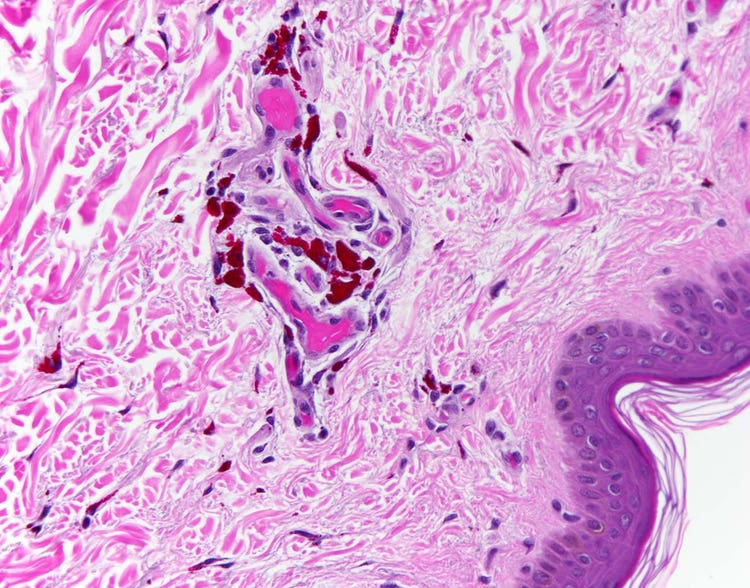

오색염색법(Pentachrome)으로 염색된 혈관을 현미경으로 관찰한 모습

5가지 서로 다른 염료를 사용하여 아세포 해부학의 다양한 측면을 부각시키는 모바트(Movat) 펜타크롬 염색법으로 염색된 인간의 정상 동맥 단면입니다. 예를 들어 혈관의 강도와 회복력을 높이는 동맥벽의 탄성섬유를 펜타크롬 염색법으로 염색하면 검은색으로 나타납니다. DP26 카메라를 사용하여 Olympus BX43 현미경으로 캡처했습니다. 이미지 제공: Marianne Hamel.